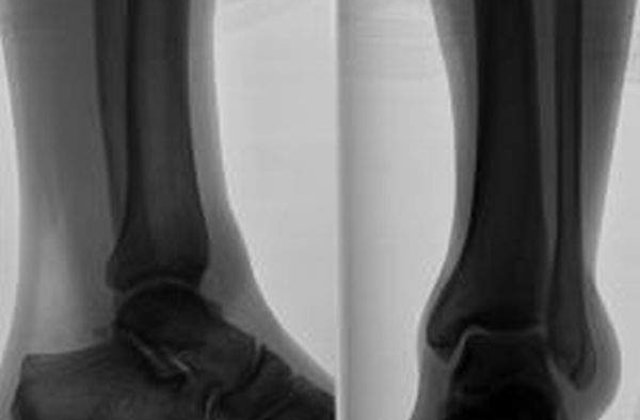

Unul dintre pacientii care au participat la testarea acestor implanturi noi, Gummi Olafsson, si-a pierdut partea inferioara a piciorului drept in urma unui accident de automobil suferit in copilarie. El spune ca noile implanturi ii permit sa isi controleze piciorul bionic aproape instantaneu. Semnalele trimise de la creierul sau catre terminatiile nervoase de la nivelul muschilor care determina miscarea au continuat chiar si atunci cand Gummi Olafsson a folosit proteze diferite, care nu erau inzestrate cu microreceptoare. Senzorii Mioelectrici Implantati (Implanted Myoelectric Sensors/ IMES) au o lungime de 5 milimetri si o latime de 3 milimetri si au fost fabricati de Fundatia Alfred Mann din Statele Unite ale Americii, care dezvolta diverse tehnologii medicale.